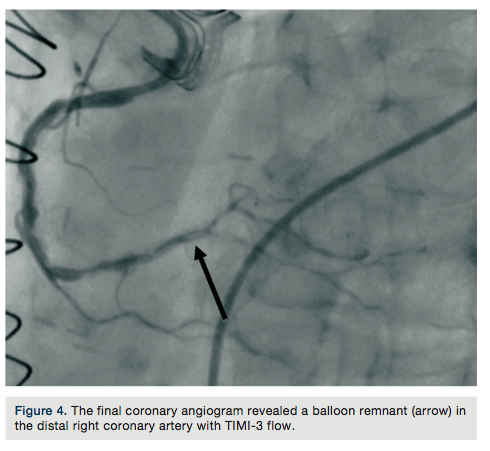

A 75-year-old female with a past medical history of coronary artery disease with previous coronary artery bypass grafting with left internal mammary artery (LIMA) to left anterior descending (LAD) artery, saphenous venous graft (SVG) to ostial medial (OM) branch, SVG to postero-lateral (PL) branch, and bioprosthetic aortic valve replacement presented with progressive dyspnea on exertion associated with substernal chest pressure. She presented with no ECG changes or elevation in cardiac biomarkers. Despite optimal medical management, she continued to endorse chest pain and thus underwent cardiac catheterization for evaluation of her coronary anatomy. Catheterization revealed a patent LIMA to LAD and SVG to OM, moderate disease in the SVG to PL graft, and a new, severe subtotal occlusion of the posterior descending artery (PDA) from the right coronary artery. We proceeded with intervention to this vessel using a 6 French (Fr) 0.75 Amplatz guide catheter. The index lesion was crossed with a Balance Middle Weight (BMW) guide wire (Abbott Vascular), with difficulty. Predilation was attempted with a 2.5 x 12 mm Apex balloon (Boston Scientific), but could not be advanced beyond the mid PDA. A GuideLiner catheter (Vascular Solutions) and a 1.25 x 10mm Sprinter Legend balloon (Medtronic) were advanced to the distal right coronary artery where they became resistant to advancement. The balloon was briefly inflated, but would still not advance. It was noted to have ruptured and despite aggressive tugging and pushing, could not be removed. The GuideLiner catheter could not be advanced further into the vessel to help free the balloon. It could also not be removed entirely, as it contained the shaft of the balloon. Eventually, with applied tension, the balloon shaft avulsed and remained in the distal RCA. Two different snares and two QuickCross catheters (Spectranetics) were advanced over the guide wire, but could not reach the site of the balloon. Given the tortuous anatomy and degree of calcification, it was determined that no other device or stent could be delivered, and thus the delivery wire was removed. Final angiography revealed TIMI-3 antegrade flow into the PDA, but with an obvious retained balloon tip and associated filling defect. Severe residual stenosis of the index lesion also remained. The patient remained hemodynamically stable throughout the procedure and asymptomatic subsequently. No ECG changes were identified and no regional wall motion abnormalities were seen on

echocardiography. The patient was placed on aspirin and warfarin, and at 3-month follow-up had not suffered any adverse consequences related to her retained balloon. At 3-month follow-up, warfarin was discontinued.